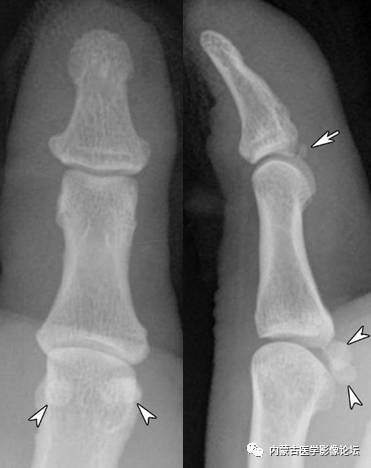

拇指籽骨:拇指指间关节籽骨(箭)较小且略呈三角形,与拇指掌指关节籽骨(箭头)不同,勿误认为撕脱骨折。